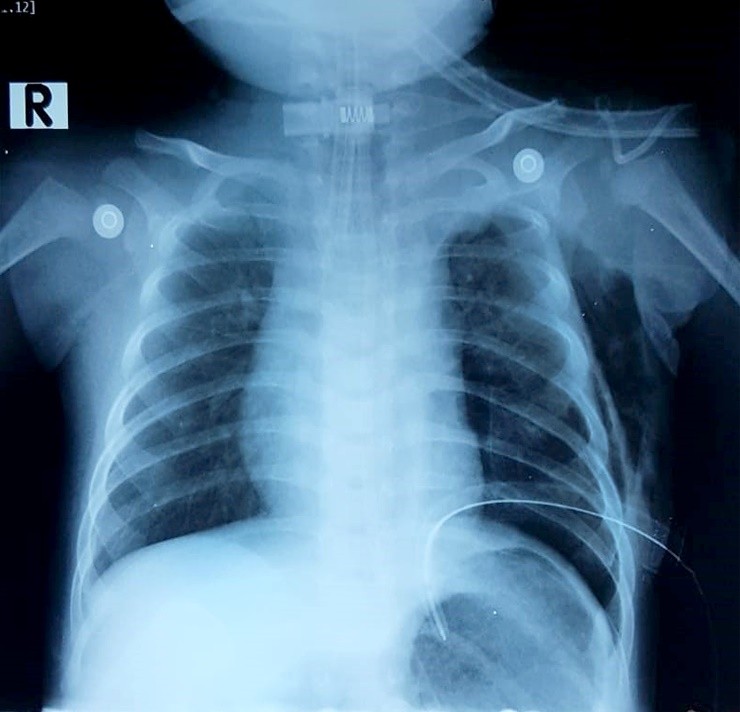

Đây là ca mổ thắt ống ngực được thực hiện lần đầu tiên bằng nội soi tại BV Nhi đồng 2 TP.HCM

Theo ThS.BS Vũ Trường Nhân - Phó Khoa ngoại - Trưởng nhóm phẫu thuật lồng ngực BV Nhi Đồng 2 TP.HCM, nguyên nhân gây tràn dịch dưỡng trấp màng phổi ở bệnh nhi này là dị dạng bẩm sinh của hệ bạch huyết vùng trung thất. Đây là ca mổ thắt ống ngực được thực hiện lần đầu tiên bằng nội soi tại BV Nhi đồng 2 TP.HCM, đánh dấu thành quả của ê kíp bác sĩ phối hợp ăn ý từ gây mê, hồi sức và chăm sóc của các khoa liên quan.